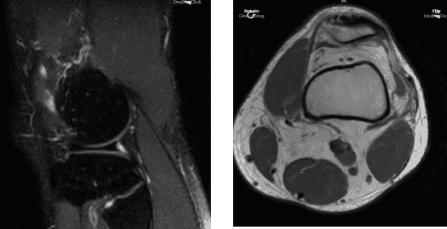

The patient presented MRI thaw showed full-thickness cartilage fissure trochlea with underlying subchondral bone marrow edema and small subchondral cysts.

MRI Left Knee Non-contrast